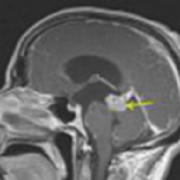

脑干星形胶质瘤怎么治疗?脑干星形胶质瘤是一种起源于脑内星形胶质细胞的恶性肿瘤,主要发生在儿童和青少年中。由于脑干是大脑的重要组成部分,负责...

脑干星形胶质瘤的治疗?脑干星形胶质细胞瘤的治疗是一个复杂且具有挑战性的过程,其难度主要取决于肿瘤的分级、位置以及患者的整体健康状况。 一、...

脑干星形胶质瘤复发率?脑干星形胶质瘤,作为一种发生于脑干部位的神经系统肿瘤,因其位置的不同性和治疗的复杂性,一直是神经外科和肿瘤学领域的一...